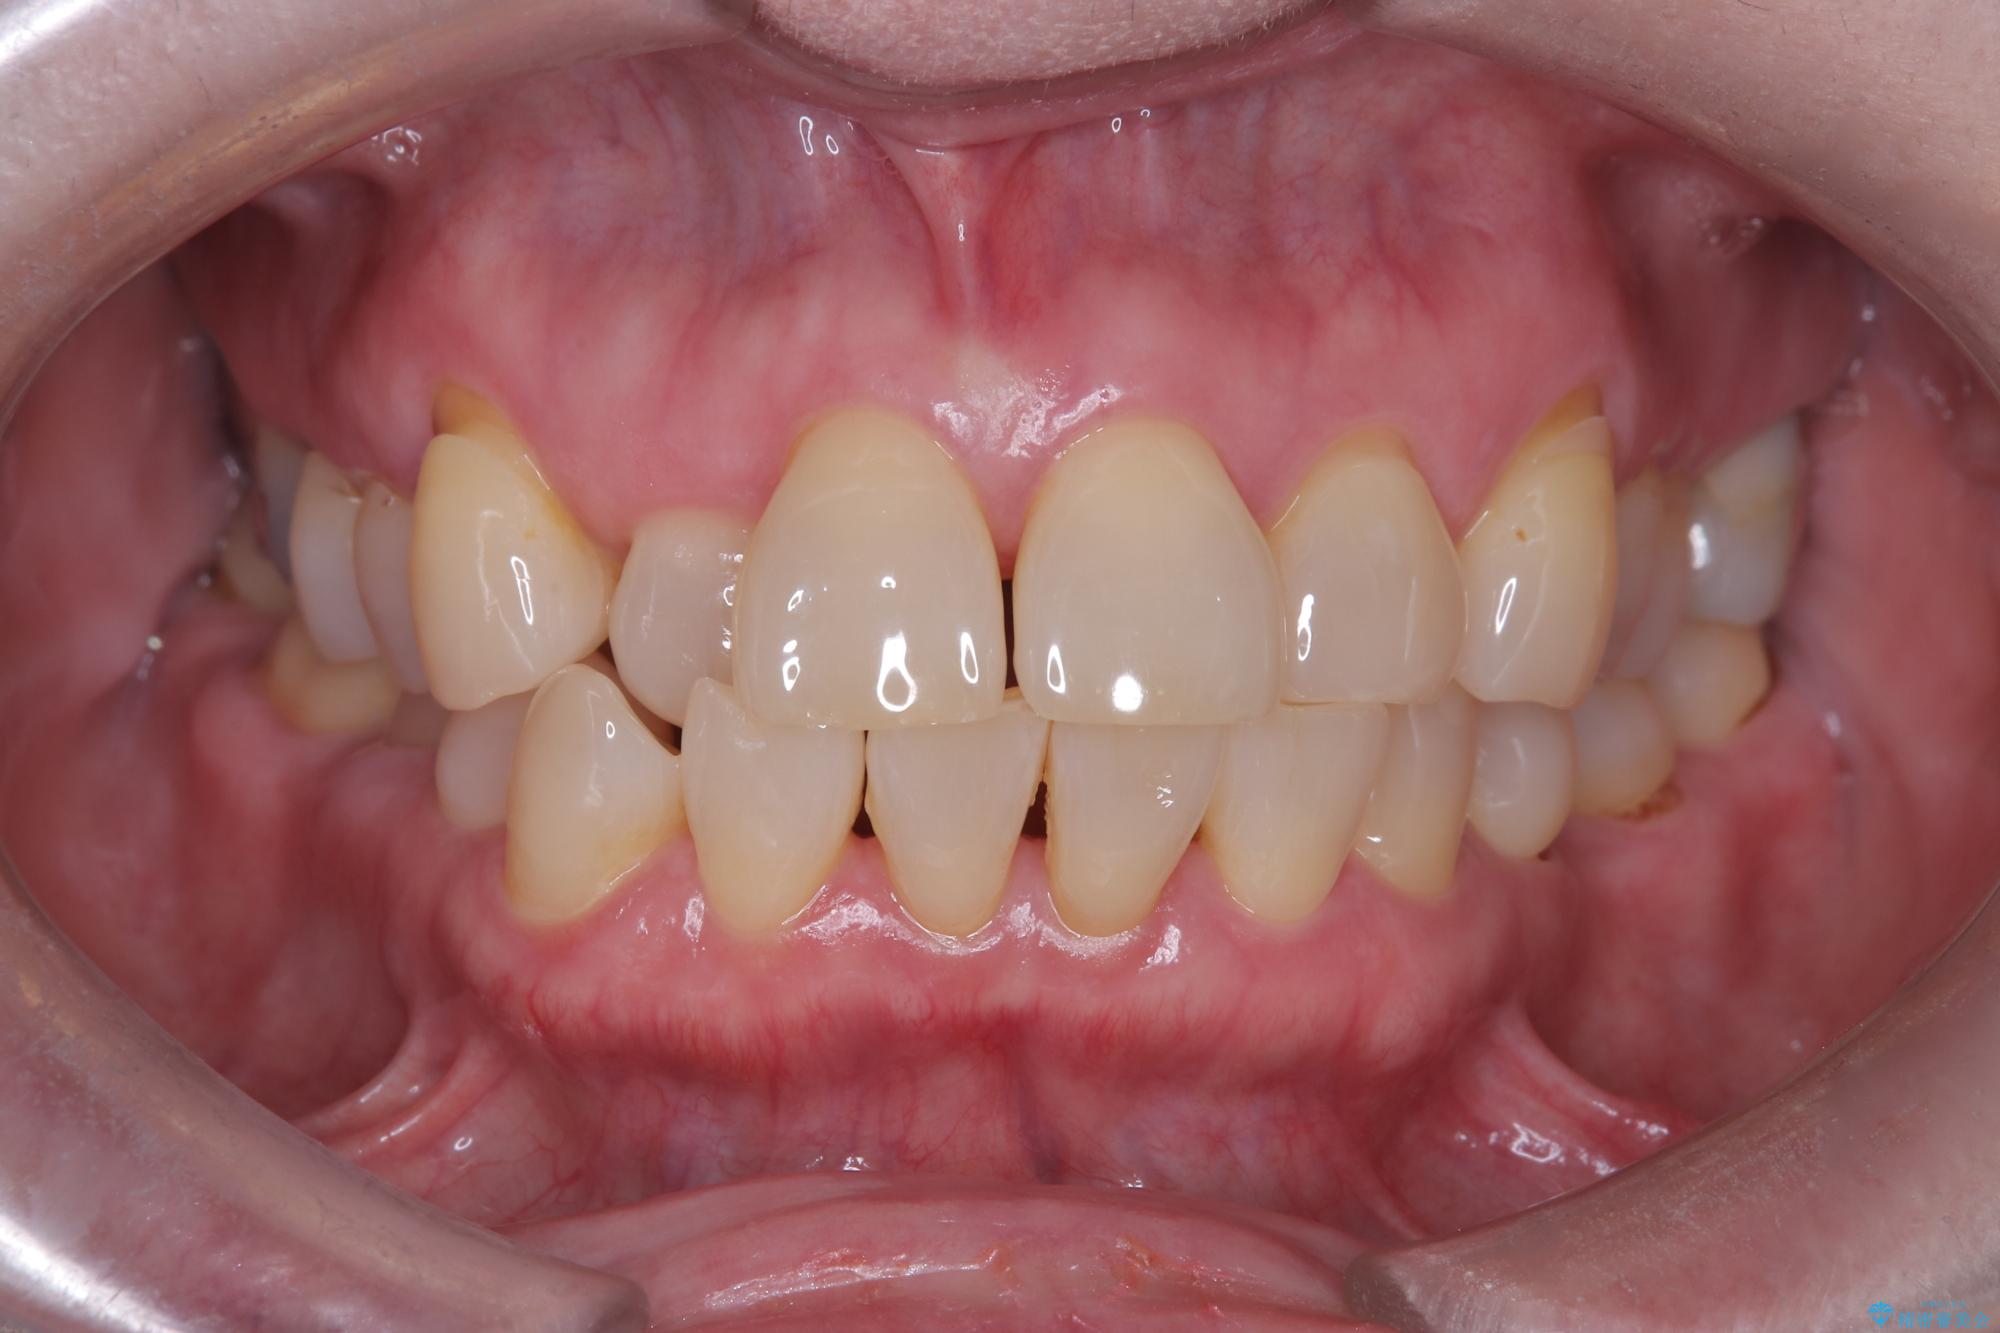

- 前歯の隙間とへこみが気になり、特に舌で触ると気になってストレスを感じるとのことで来院された患者様です。

上下ともに軽度の叢生があり、下顎がやや前突傾向にあったため、本来であれば矯正治療が第一選択となります。矯正によって下の前歯を後方に移動させることで、咬み合わせの改善とともに前歯のデコボコも整えることができます。

そのため今回は、右上2番を抜歯し、右上1番および左上1番をオールセラミッククラウンで審美的に修復しました。

上下に叢生(歯のデコボコ)と反対咬合があるため、本来であれば矯正治療が最も理想的な治療選択となります。